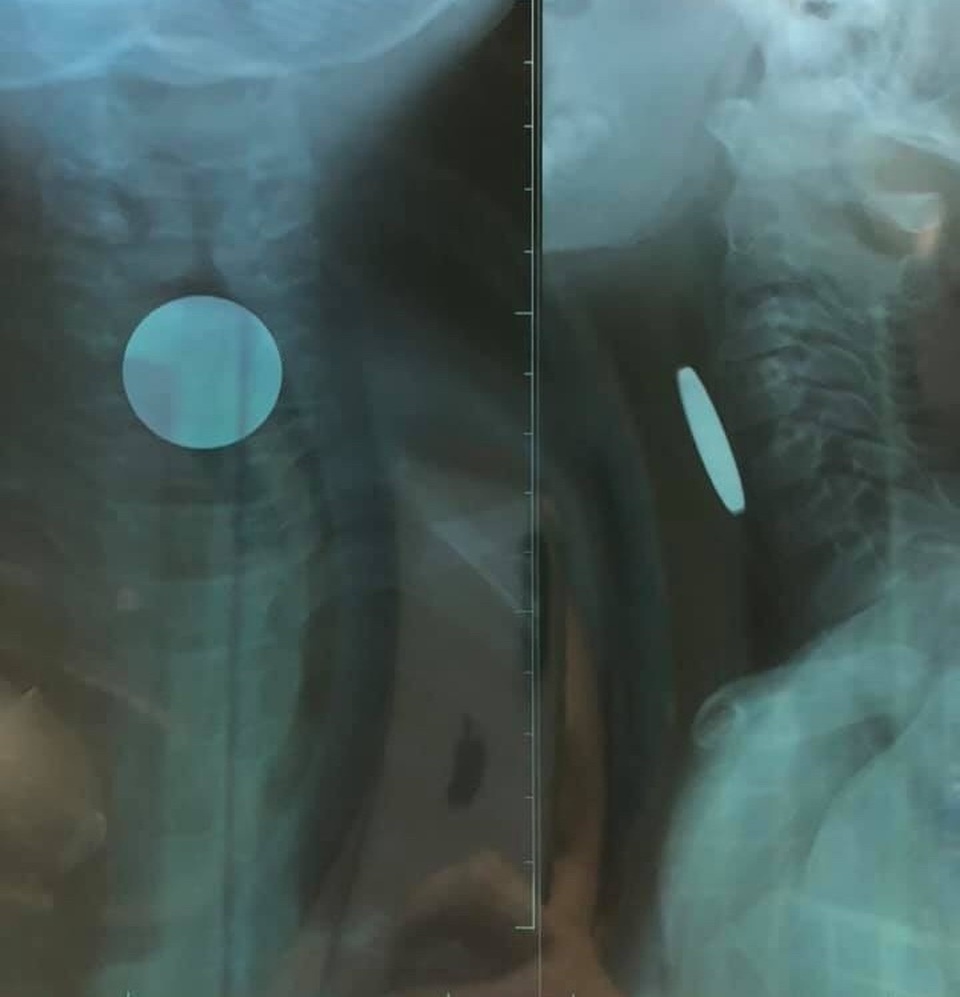

Đồng xu trong thực quản cháu bé 5 tuổi

Qua thăm khám và chụp X-quang, các bác sỹ phát hiện có dị vật (đồng xu) đoạn thực quản cổ có đường kính 24mm. Sau khi tiến hành nội soi dưới gây mê và gắp đồng xu ra, bệnh nhi P. đã ổn định và có thể xuất viện.